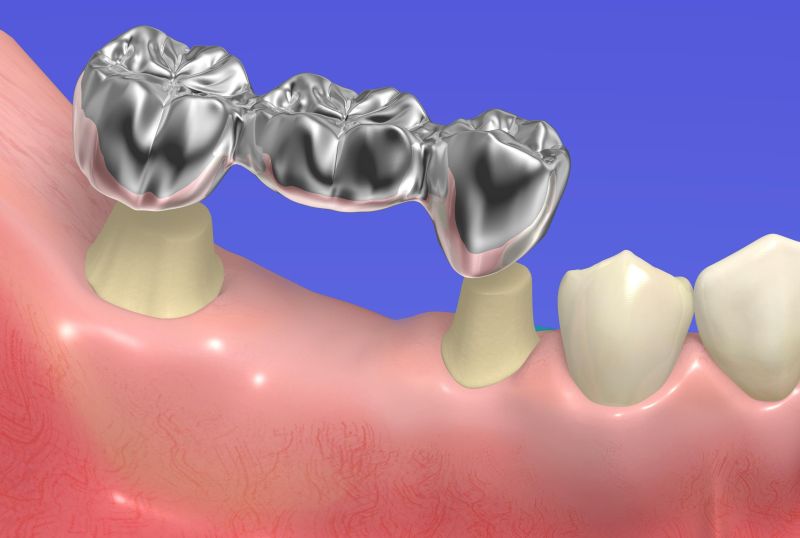

歯を喪失した場合、放置していると周囲の歯に負担がかかり、さらに歯を失ってしまったり、嚙み合わせの悪化を招いたりする可能性があります。

入れ歯は、ただ噛めるようになることだけが目的ではなく、残っている歯が動くのを防ぐ大切な目的があります。

差し歯の種類は保険適用のものや適用外のもの、素材も様々ですので、ご相談ください。

また、両隣の歯を土台にして、橋をかけるように人工歯を設置するブリッジ治療もあります。

ブリッジは固定式なので、取り外したり、装置を洗ったりする手間はありません。

しっかりと両隣の歯に固定されているために、食事の際も、違和感なく食べることができます。